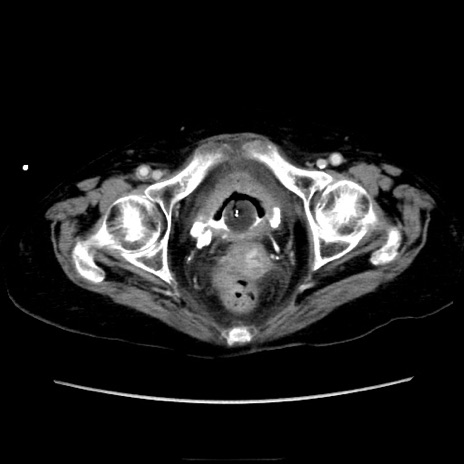

症例40(横断像)

横断像